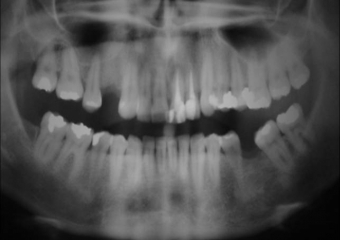

Raio X Inicial